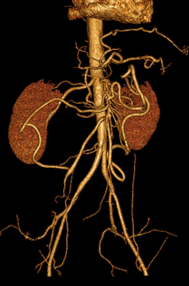

Foie : maladie chronique

DANSE E. - UCL

MASTER 1